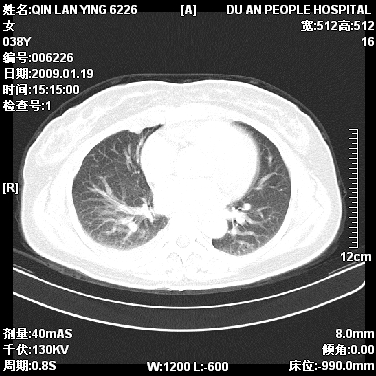

女,38岁,胸疼1个月。wbc:1万4

1)右肺中央型肺癌并右肺上叶阻塞性肺炎、节段性肺不张,纵隔淋巴结转移、右侧胸膜转移、肝脏转移。2)右侧胸腔少量积液。

1、右侧中央型肺癌并阻塞性肺不张,纵隔内、主动脉弓旁、右肺门淋巴结及肝脏转移可能性大,建议纤支镜进一步检查。

2、右侧胸腔积液。

本病例有几个容易诊断的地方:1、右肺上叶前段支气管闭塞,肺不张。2、淋巴结明显肿大。3、肝脏多个类圆形低密度影呈“牛眼征”改变,高度提示转移。

从影像学角度分析      右肺上叶中央型肺癌,并阻塞性不张、肺炎,纵隔淋巴结、膈顶淋巴结转移。